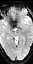

functional data of the sub62966 in the part 4 may be bad. I'm not

sure whether the problem arises from wrong data scanning, or wrong

data transforming.